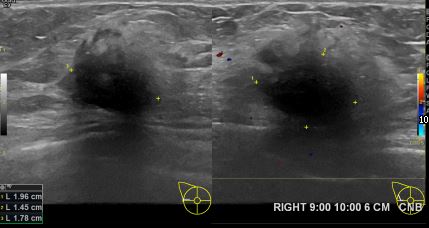

아산유외과개원후 650번째 유방암진단

상기환자 외부검사상 이상소견으로 내원하신 70대여성으로 우측유방의 의심스러혹

조직검사시행해 유방암 진단되었습니다.